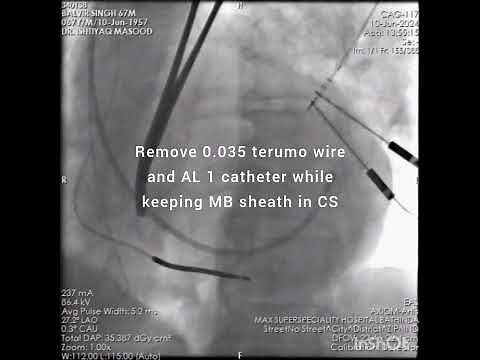

Cardiac Resynchronization Thera…